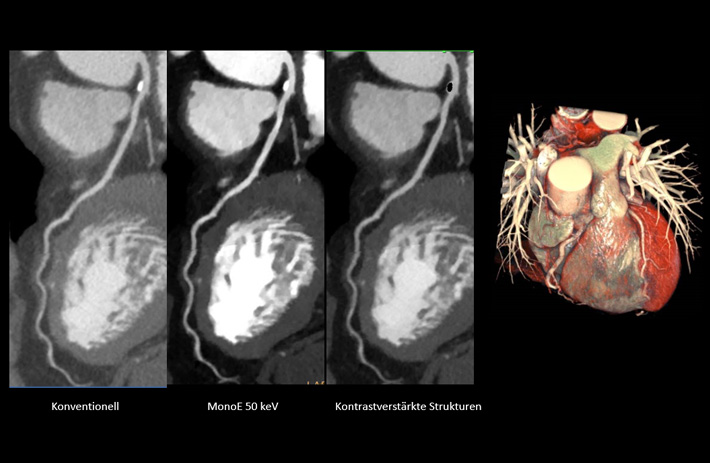

Mit dem Spektral-Detektor-CT werden Spektraldaten automatisch bei jedem Scan erfasst. Die Informationen stehen jederzeit auf der Scankonsole, der CT-Workstation sowie an jedem PACS-Arbeitsplatz zur Verfügung, sodass es nicht notwendig ist, den Patienten erneut zu scannen, bspw. wenn initial zufällige Anomalien festgestellt wurden. Dadurch profitieren Anwender durch eine höhere Diagnosesicherheit und weniger Nachuntersuchungen auf anderen bildgebenden Systemen. Unsere Fallsammlung zeigt, welchen klinischen Mehrwert der Spektral-Detektor-CT in unterschiedlichsten Anwendungsbereichen in der klinischen Routine bringt. Jede Woche gehen neue Fälle live.